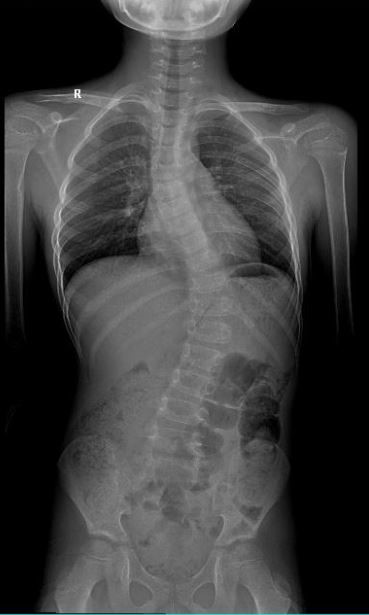

男 15岁

脊柱侧弯畸形

AEC 80KV

脊柱侧弯畸矫形术前检查

通过全景拼接图像可以清晰显示脊柱侧弯的具体细节,为矫形手术提供更详尽的资料。